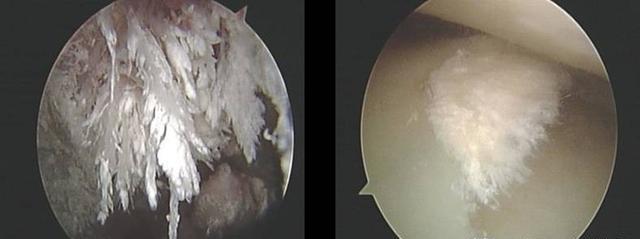

痛风石偏光显微镜检查影像。

针刀镜检尿酸结晶沉积。